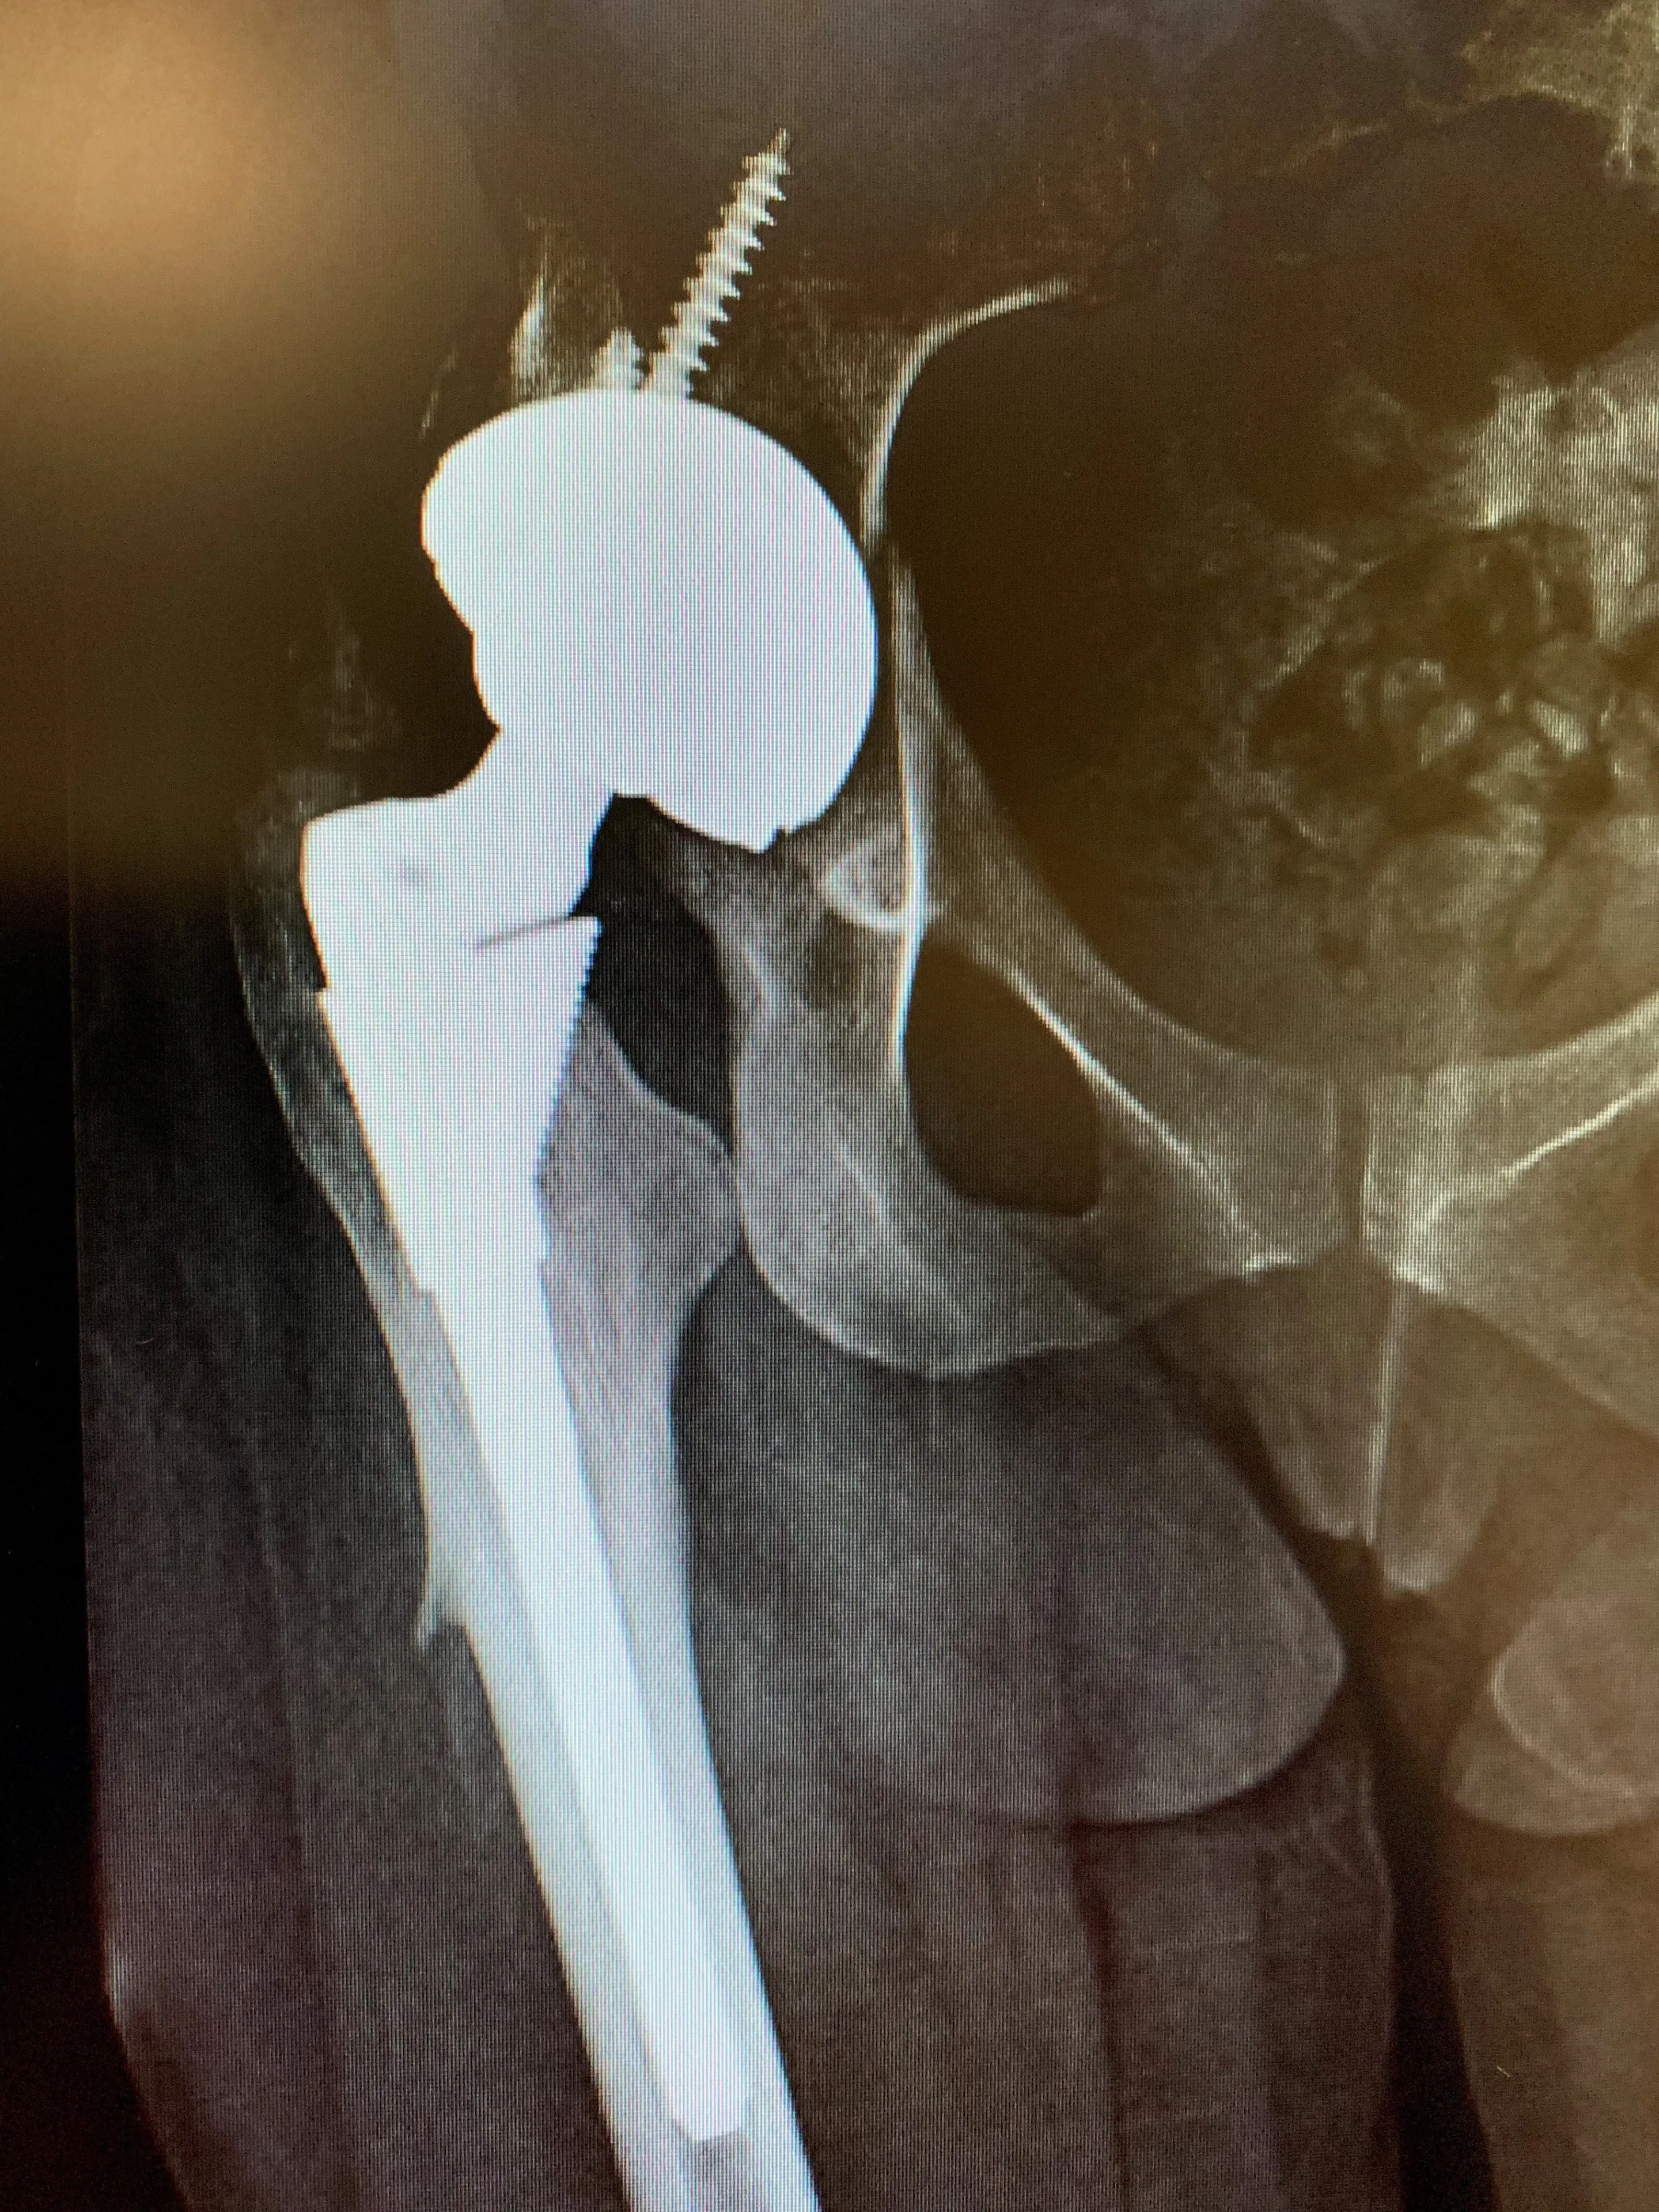

Post-op

She is a non-smoker. We performed the revision surgery through a lateral approach – the approach used for her initial hip replacement. We exposed her artificial hip fully, and removed her acetabular component only.

Our plan was to exchange this component for an alternative that facilitated a dual-mobility construct – one that has proven to address the problem of instability very well.

This was done without event and, on extensive stability testing, no dislocations were observed. Post-operatively, Miss EM underwent extensive physiotherapy to strengthen her abductors as much as possible – another strategy to address her problem of instability. 1 year post-op, she does still complain of stiffness in her hip, but has not experienced any further dislocations.